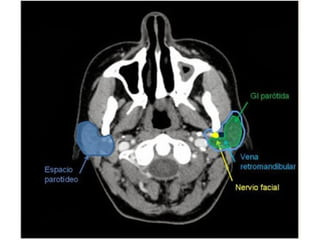

ESPACIO PAROTÍDEO.

 Localizado lateralmente al espacio parafaríngeo y

delimitado por la capa superficial de la fascia cervical

profunda. En muchas ocasiones comunica libremente con

el espacio parafaríngeo preestiloideo por ausencia de

fascia entre ambos espacios. Contiene la glándula

parótida, la porción intraparotídea del nervio facial,

ganglios intraglandulares, arterias carótida externa y

maxilar interna, y vena retromandibular.

 Una lesión maligna puede tener diseminación perineural

hacia el hueso temporal a través del nervio facial.